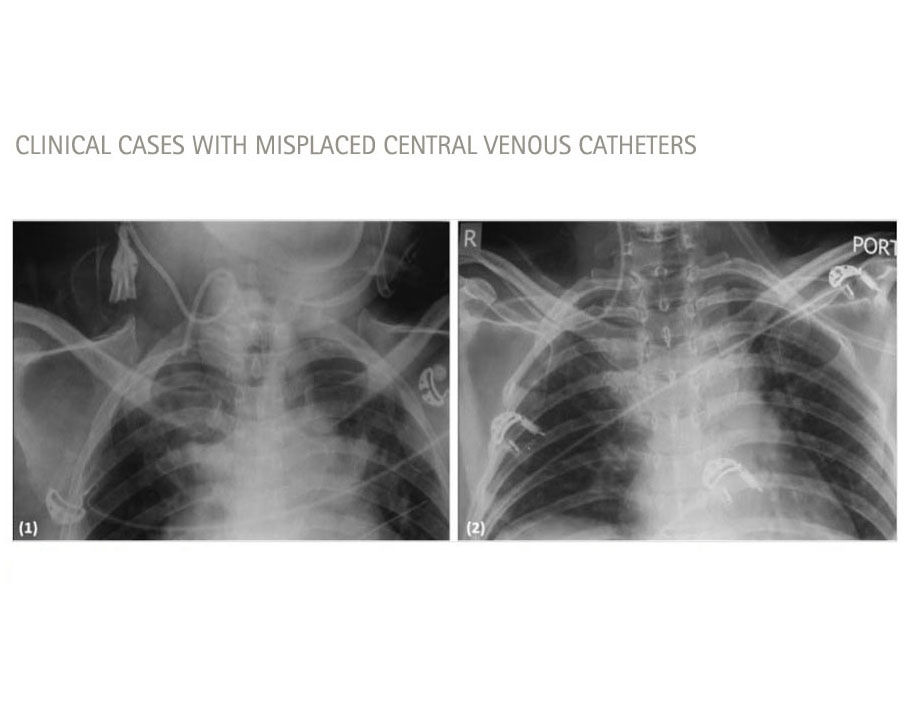

Type and Position of Catheter Misplacement 12

Intravascular Misplacement

Extravascular Misplacement

Carotid arteryExtradural space

Azygos veinPericardium

Paersistent left sided superior vena cavaPleural space

Internal thoracic (mammarx) veinMediastinum

Vertebral veinThoracic duct

Medica Image to detect misplaced catheter, chest X-ray, alternatively CT or MRI